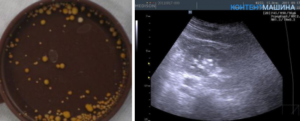

- Ультразвукового исследования – определение микролитиаза (выявление маленьких камней различной структуры).

- УЗИ;

УЗИ почек и мочевого пузыря показывает наличие камней в лоханках, в мочеточниках.

К сожалению, оксалатные камни менее 6 мм размером чрезвычайно плохо визуализируются по УЗИ, поэтому даже при «чистой» ультразвуковой картине, но при наличии характерных отклонений в моче рекомендуется выполнение рентгенографии (урографии).